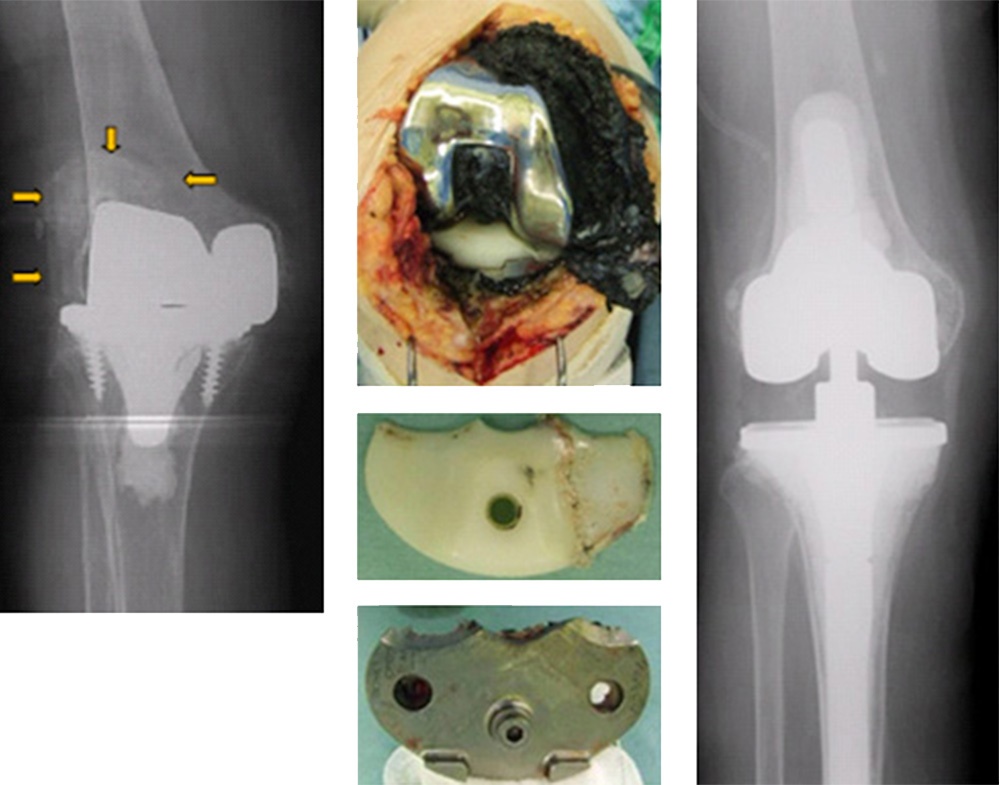

人工膝関節再置換術

人工関節の約9割は20年後もうまく機能しておりますが、残りの人は入れ替えが必要になります。その原因には感染、人工関節の緩み、骨融解(骨がとけてくる)などが上げられます。特に人工関節の緩みが最も多く、人工関節の再置換(入れ替え)が必要になります。放置するとどんどん悪化し、手術がさらに困難になりますので、緩み等が明らかとなった場合には早急な手術が必要となります。

人工関節の緩み、人工関節周囲の骨融解像(骨が解けている)を認める。

手術中の写真:人工関節のプラスチックが磨り減っているのがわかる。

人工関節の再置換術(入れ替えの手術)を行った。

人工関節の緩み、人工関節の亜脱臼(ずれている)、人工関節周囲の骨融解像(骨がとけている)、そして白くもやもやした影を認める。

手術中の写真:関節内が黒くなっている(金属が磨り減って金属粉が関節内に蓄積している)、人工関節の金属とプラスチックが磨り減っているのがわかる。